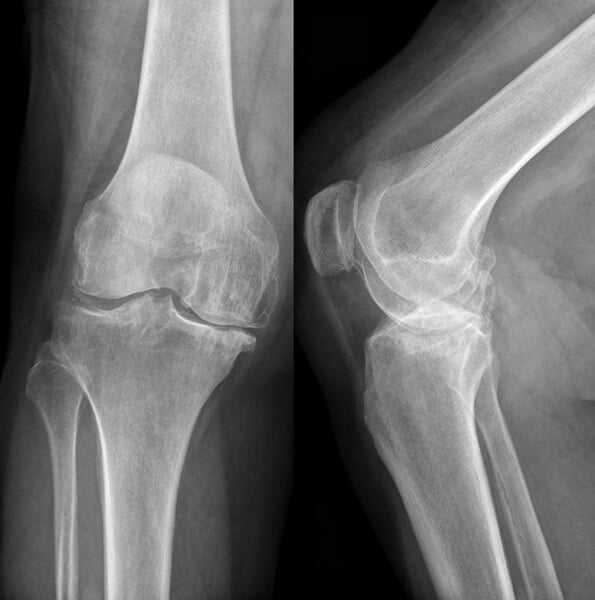

Самым объективным методом является рентгенография, с помощью которой определяется сужение поврежденного отдела суставной щели с признаками деформирующего артроза.

Для правильной диагностики травмы латерального мениска необходимо точно собрать анамнез, то есть сведения как именно произошла травма и что послужило ее причиной. При предварительном выявлении проблемы и чтобы исключить переломы костей, используют рентгенологическое исследование. Чтобы точно определить какой произошел разрыв медиального или латерального хрящевого диска, нужно провести магнитно-резонансную томографию.

- Рентгенографическая визуализация – проводится при помощи рентгеновских лучей, после чего получают изображение структур на специальной фотопленке или экране. Исследование позволяет выявить выраженные нарушения. Для более точного установления их локализации рентгенография выполняется в проекции прямо и сбоку.

Рентгенологическое исследование – довольно простой способ диагностики. На рентгенологических снимках мениски не видны, поэтому проводят исследования с применением контрастных веществ или применяют более современные методы исследования.